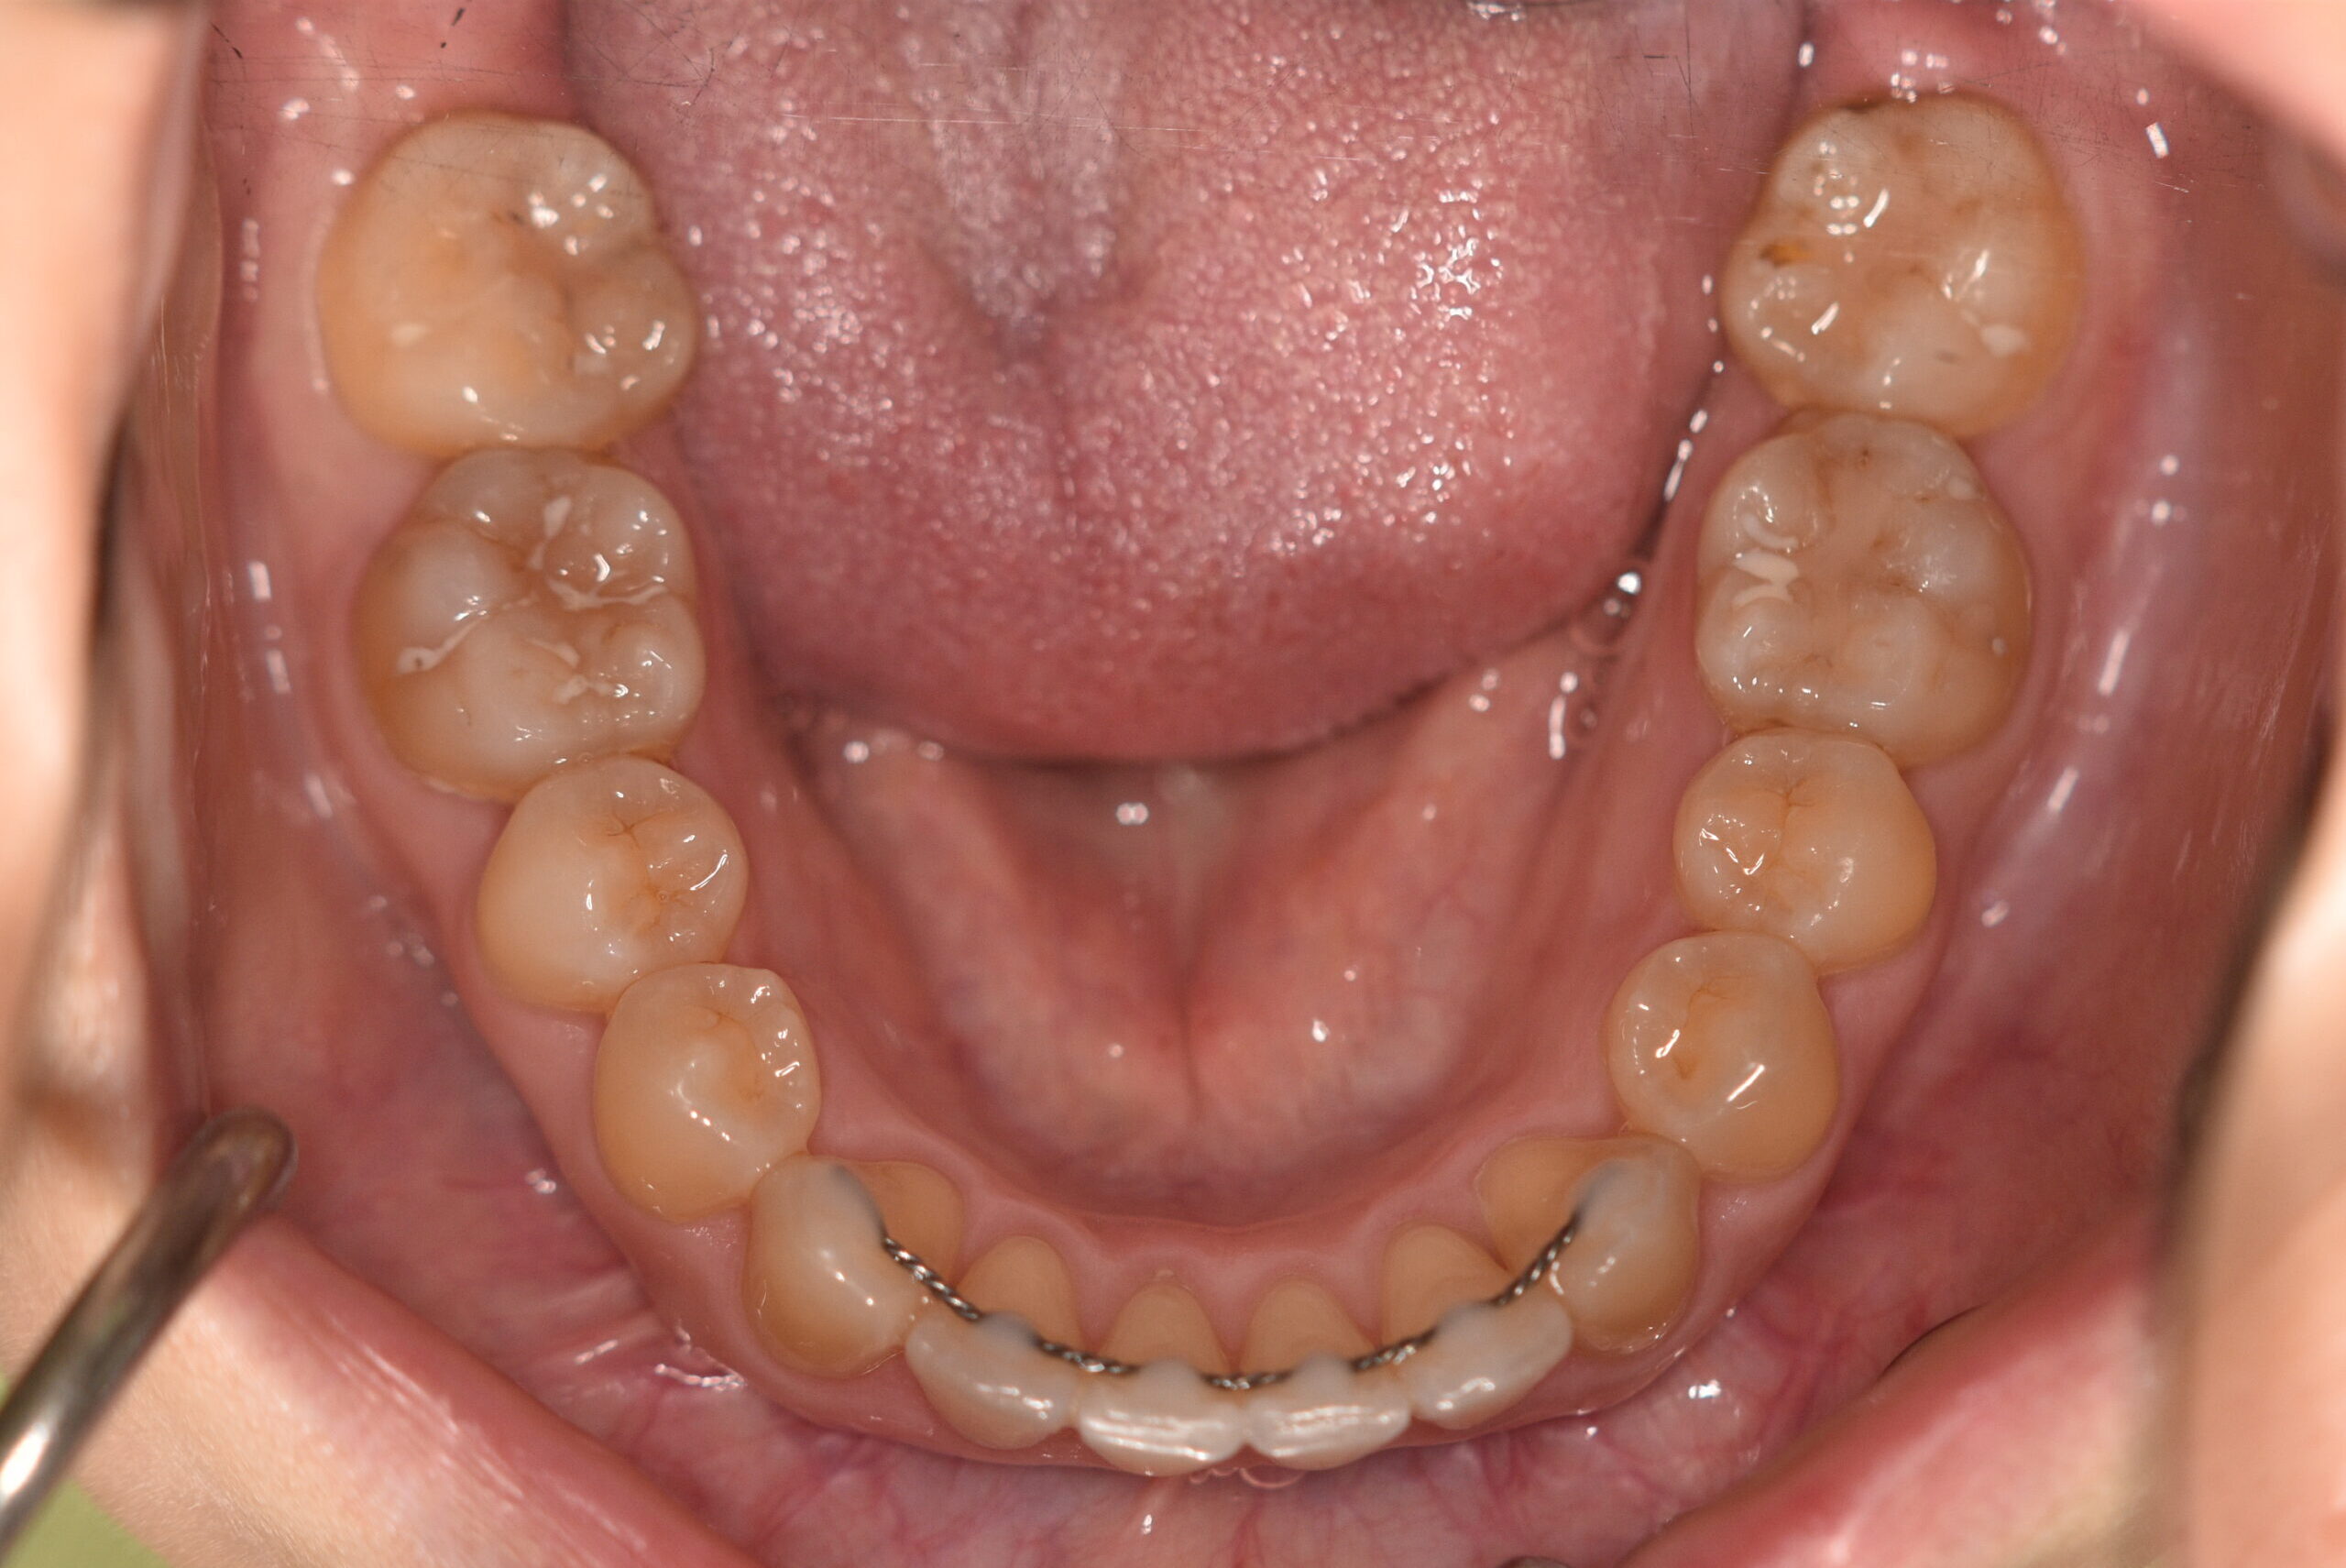

動的治療終了時

症例 症例 症例 症例 症例